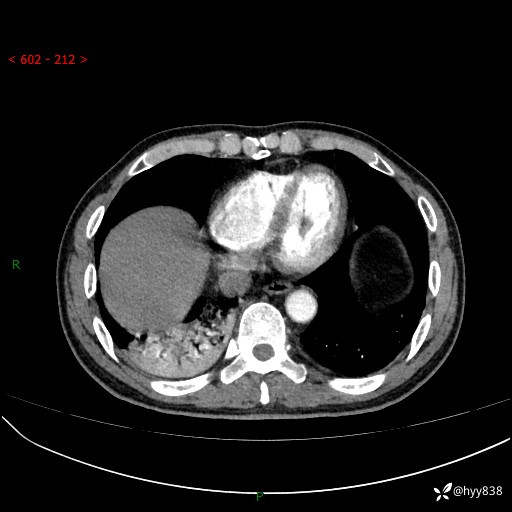

63岁/男,发热5余天。精彩好病例,“大叶性肺炎”,等你来诊---结果公布~

【患者信息】:63岁/男

【主诉】:发热5余天

【现病史及既往史】:患者5余天无明显诱因出现畏寒寒战发热,最高体温39.5℃,发热无明显昼夜规律,伴全身乏力、头晕,无头痛、无咳嗽咳痰、无胸痛咯血、无气短、无腹痛腹泻、无尿频尿急尿痛等不适,于当地市第五人民医院就诊,予以抗感染等治疗(具体不详)后发热无明显好转,1天前查胸部CT提示右下肺感染,为求进一步诊治,门诊以“社区获得性肺炎”收治入院; 起病以来,患者精神、食欲一般,睡眠可,大小便正常,体力体重较前无明显变化。

【检查】:胸部CT增强